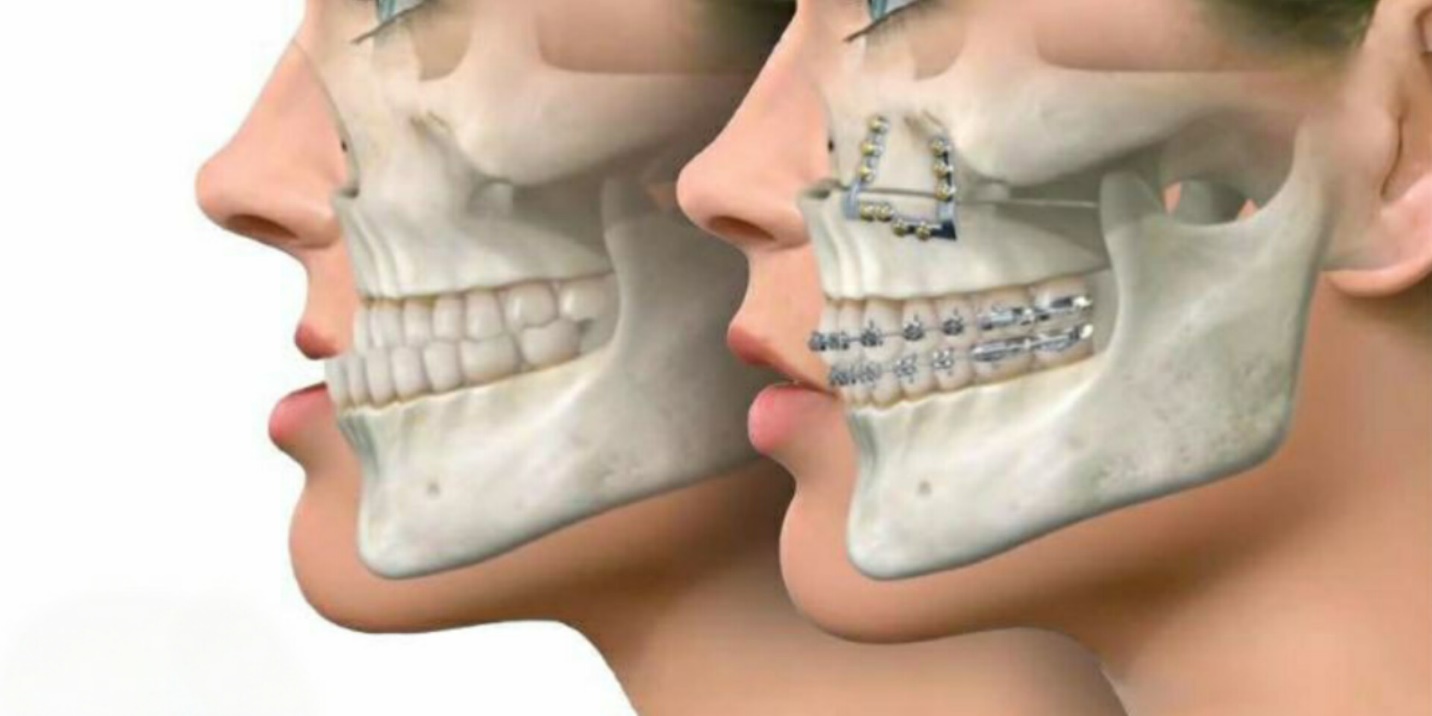

ارتودنسی مستقیماً بر موقعیت فکها، نحوه قرارگیری دندانها و در نتیجه بر تناسب اجزای صورت اثر میگذارد. فک بالا و پایین چارچوب اصلی قسمت پایینی چهره را تشکیل میدهند و هرگونه تغییر در زاویه یا موقعیت آنها میتواند ظاهر صورت را دگرگون کند.

وقتی دندانها در جای صحیح خود قرار میگیرند، لبها بهتر بسته میشوند و چهره از نمای نیمرخ متعادلتر به نظر میرسد. از دیدگاه علمی، بهبود تراز بایت و اصلاح ناهنجاریهای فکی به هماهنگی میان دهان، بینی و چانه کمک میکند. بنابراین، ارتودنسی صرفاً برای زیبایی دندانها نیست؛ بلکه نقشی کلیدی در بازگرداندن توازن ساختاری چهره دارد.

▪️ تغییر در فک بالا و پایین

اصلاح ناهنجاریهای فکی مهمترین عاملی است که پس از ارتودنسی میتواند فرم چهره را تغییر دهد. در صورتی که فک بالا جلوتر از حد طبیعی باشد، چهره از نمای نیمرخ برجسته به نظر میرسد و درمان ارتودنسی با تنظیم موقعیت فک، این جلوآمدگی را متعادل میکند.

در مقابل، افرادی که فک پایین آنها عقب است، پس از درمان، ظاهر فکشان برجستهتر و زاویه صورتشان طبیعیتر میشود. این تغییرات باعث هماهنگی بیشتر بین فک، لب و بینی خواهد شد.

▪️ تغییر در چانه و زاویه فک

وقتی فک پایین به موقعیت طبیعی خود بازگردانده میشود، ظاهر چانه نیز تغییر میکند. در بیماران مبتلا به عقبرفتگی فک پایین، پس از ارتودنسی، چانه برجستهتر و زاویه صورت واضحتر میشود. در مقابل، در فکهای جلو آمده، چانه کمی به عقب بازمیگردد و نمای نیمرخ ملایمتر میشود.

▪️ براکتهای ثابت سنتی

درمان با براکتهای فلزی سنتی بیشترین کنترل را بر حرکت دندانها دارد. با تنظیم دقیق نیروهای ارتودنسی، میتوان موقعیت دندانها را با دقت بالا تغییر داد و اثر مشخصی بر فرم فک و لبها ایجاد کرد.

▪️ ارتودنسی فانکشنال برای اصلاح فک

در بیماران کمسنتر، وسایل فانکشنال میتوانند رشد فک را هدایت کنند. این نوع درمان تأثیر زیادی بر زاویه فک، چانه و هماهنگی نیمرخ دارد و در صورت اجرای درست، میتواند ساختار فکی را بهطور قابلتوجهی تغییر دهد.